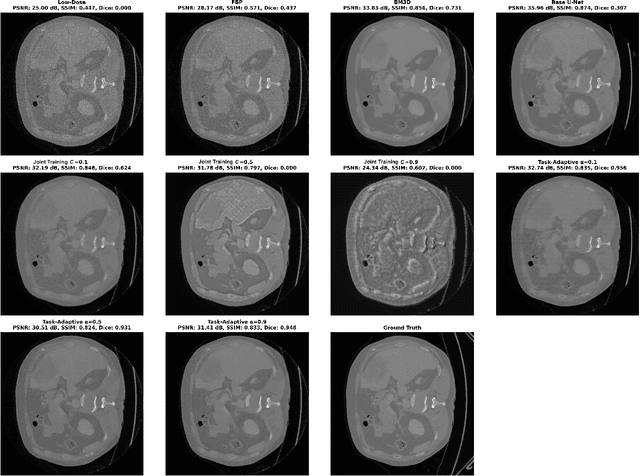

Deep learning-based low-dose computed tomography reconstruction methods already achieve high performance on standard image quality metrics like peak signal-to-noise ratio and structural similarity index measure. Yet, they frequently fail to preserve the critical anatomical details needed for diagnostic tasks. This fundamental limitation hinders their clinical applicability despite their high metric scores. We propose a novel task-adaptive reconstruction framework that addresses this gap by incorporating a frozen pre-trained task network as a regularization term in the reconstruction loss function. Unlike existing joint-training approaches that simultaneously optimize both reconstruction and task networks, and risk diverging from satisfactory reconstructions, our method leverages a pre-trained task model to guide reconstruction training while still maintaining diagnostic quality. We validate our framework on a liver and liver tumor segmentation task. Our task-adaptive models achieve Dice scores up to 0.707, approaching the performance of full-dose scans (0.874), and substantially outperforming joint-training approaches (0.331) and traditional reconstruction methods (0.626). Critically, our framework can be integrated into any existing deep learning-based reconstruction model through simple loss function modification, enabling widespread adoption for task-adaptive optimization in clinical practice. Our codes are available at: https://github.com/itu-biai/task_adaptive_ct